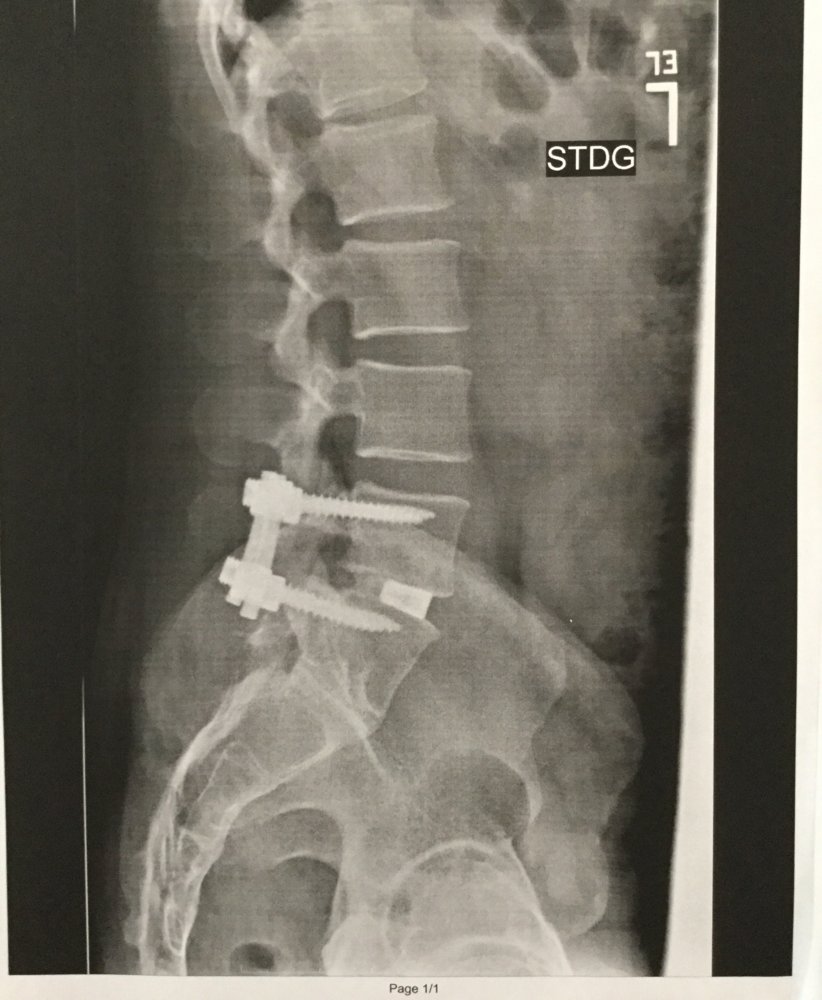

Hey, I could have made you an appliance like that, with the junk I got. No charge!3 months since my 3rd back surgery. Started run-walk on the treadmill this week. Tonight it was 2-minute walk then 30-second run, repeat... My legs feel like jello, but I’m thankful to be where I am!